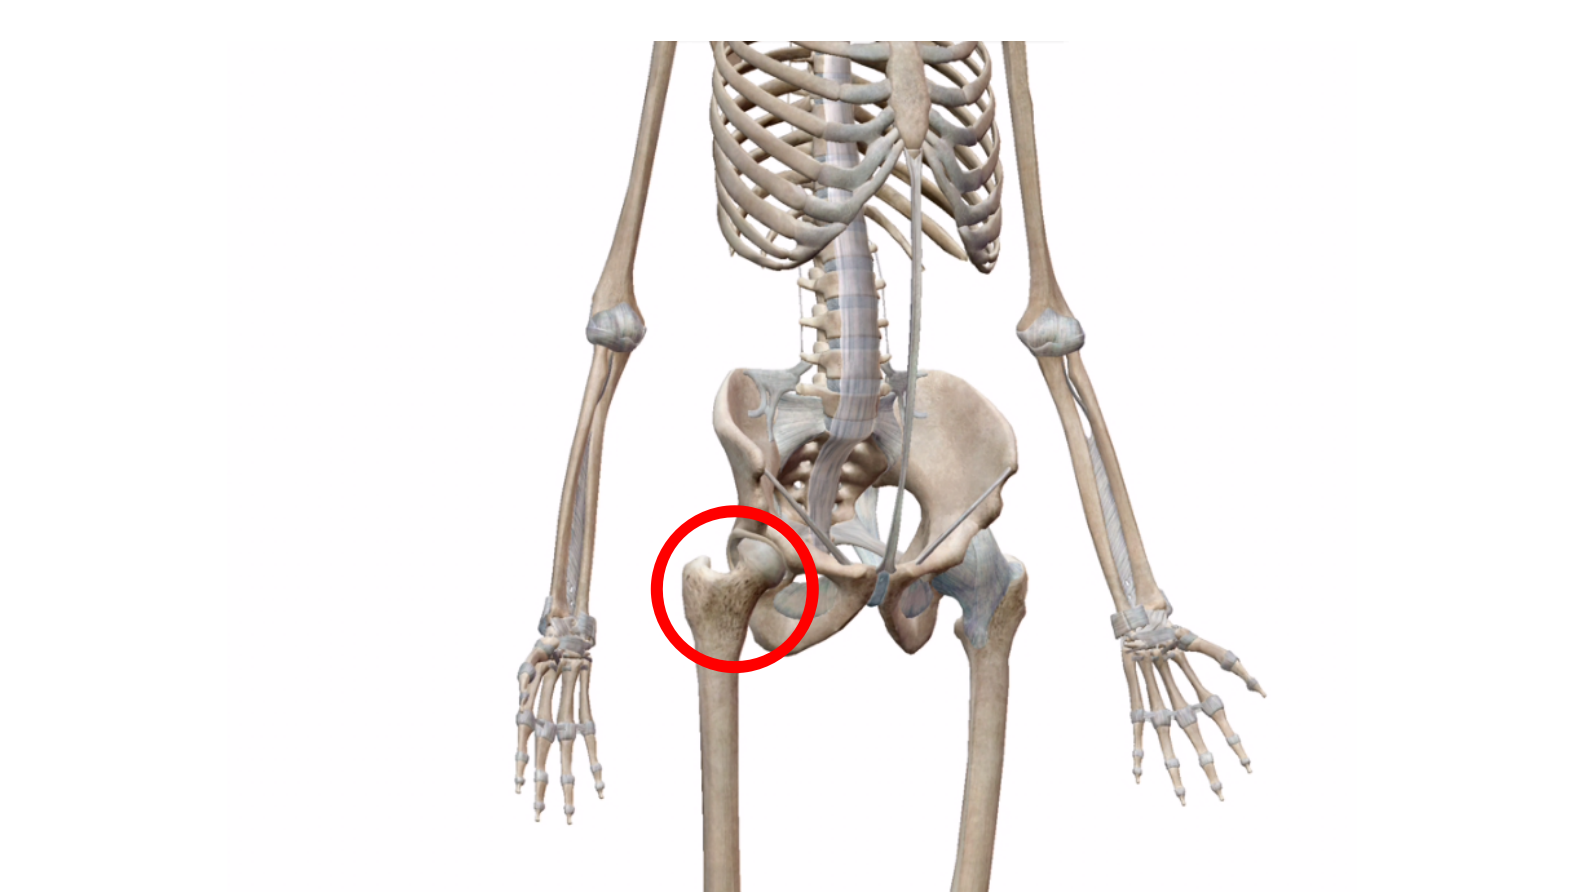

話しは出来ますが、股関節と右足が痛みと腫れで痛くて動かせないとのこと。

・股関節 捻挫